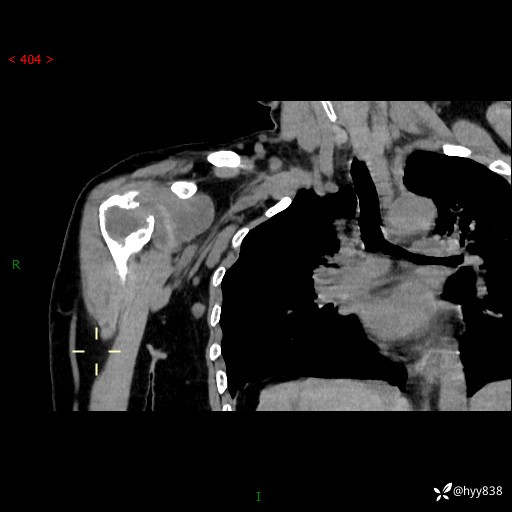

右肩关节CT平扫